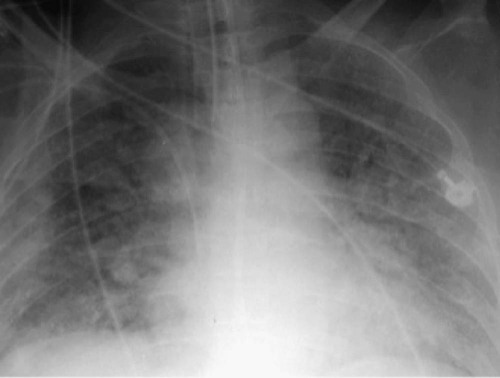

The first description of ARDS appeared in a remarkable case series reported in 1967.7 Ashbaugh and colleagues described 12 patients ranging in age from 11 to 48 years who presented with respiratory distress, hypoxemic respiratory failure, and patchy bilateral opacities on chest radiographs (Fig. 100-2). Most of the cases were preceded by severe trauma or viral infection and the onset of symptoms was relatively rapid, with most patients developing respiratory distress within 48 to72 hours of the beginning of their illness. Many patients required positive pressure ventilation and exhibited low respiratory system compliance, and some experienced improvement in oxygenation with the application of positive end-expiratory pressure (PEEP). This syndrome was initially termed the adult respiratory distress syndrome to distinguish it from the respiratory distress syndrome seen in infants. Subsequently, recognizing that the syndrome can also develop in children, it was renamed the acute respiratory distress syndrome.